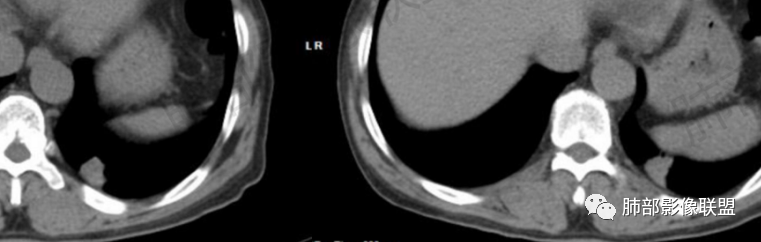

晨读:左肺下叶胸膜下实性结节影边缘毛糙,有毛刺,分叶,近段支气管未见显示,可能堵塞,远端宽基底与胸膜相贴,边缘平直,部分彭隆,病灶局限、单发,无增强,不好判断肿瘤血供,临床男性,63岁,无症状,体检发现,有吸烟史,考虑恶性:腺癌,鳞癌,小细胞肺癌,鉴别:肺隐球菌建议增强及穿刺检查。

老年男性,吸烟史。左下肺外周结节,糊墙,部分边缘平直、部分膀隆,见分叶,支气管截断?部分边缘似乎有GGO,内部情况不详。整体考虑恶性,腺癌可能性大,注意鉴别鳞癌、炎性肉芽肿。

晨读病例,老年人 ,吸烟史,左肺下叶结节影,密度均匀,边缘毛糙,周围可见长毛刺,病灶边缘分叶,局部膨隆,部分边界平直,收缩,病灶相邻胸膜处可见糊墙征象,病灶近肺门处见支气管堵塞,考虑恶性病变,周围型肺癌:鳞癌伴肺不张>腺癌,鉴别隐球,炎性假瘤。

边缘平直为主,部分膨隆,糊墙征

2、影像表现:无肺气肿背景、定位左肺下叶后基底段,不规则结节、与支气管关系不明确,部分边缘平直、部分膨隆,病变与胸膜宽基底相连,病变与胸膜糊墙征,病变周围见细、长、软毛刺,病变密度比较均匀。影像总体倾向炎症、符合肺组织慢性炎症伴机化。